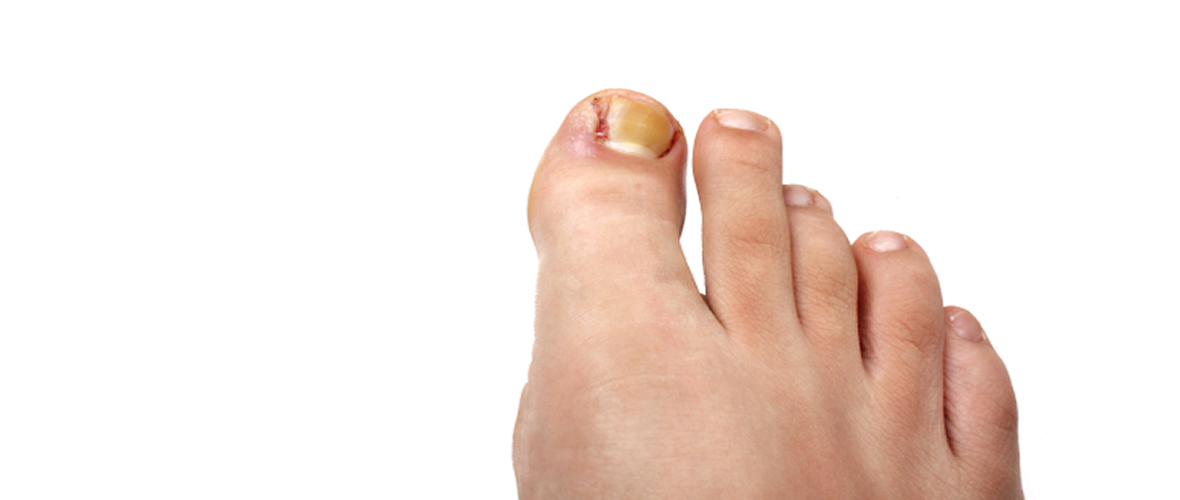

Ingrown Toenail Treatment

Ingrown toenails are due to the penetration of the edges of the nail plate into the soft tissue of the toe. It begins with a painful irritation that often becomes infected. With bacterial invasion, the nail margin becomes red and swollen often demonstrating drainage or pus.

Treatment for ingrown toenails is relatively painless

Ingrown Toenail Treatment - Read More...